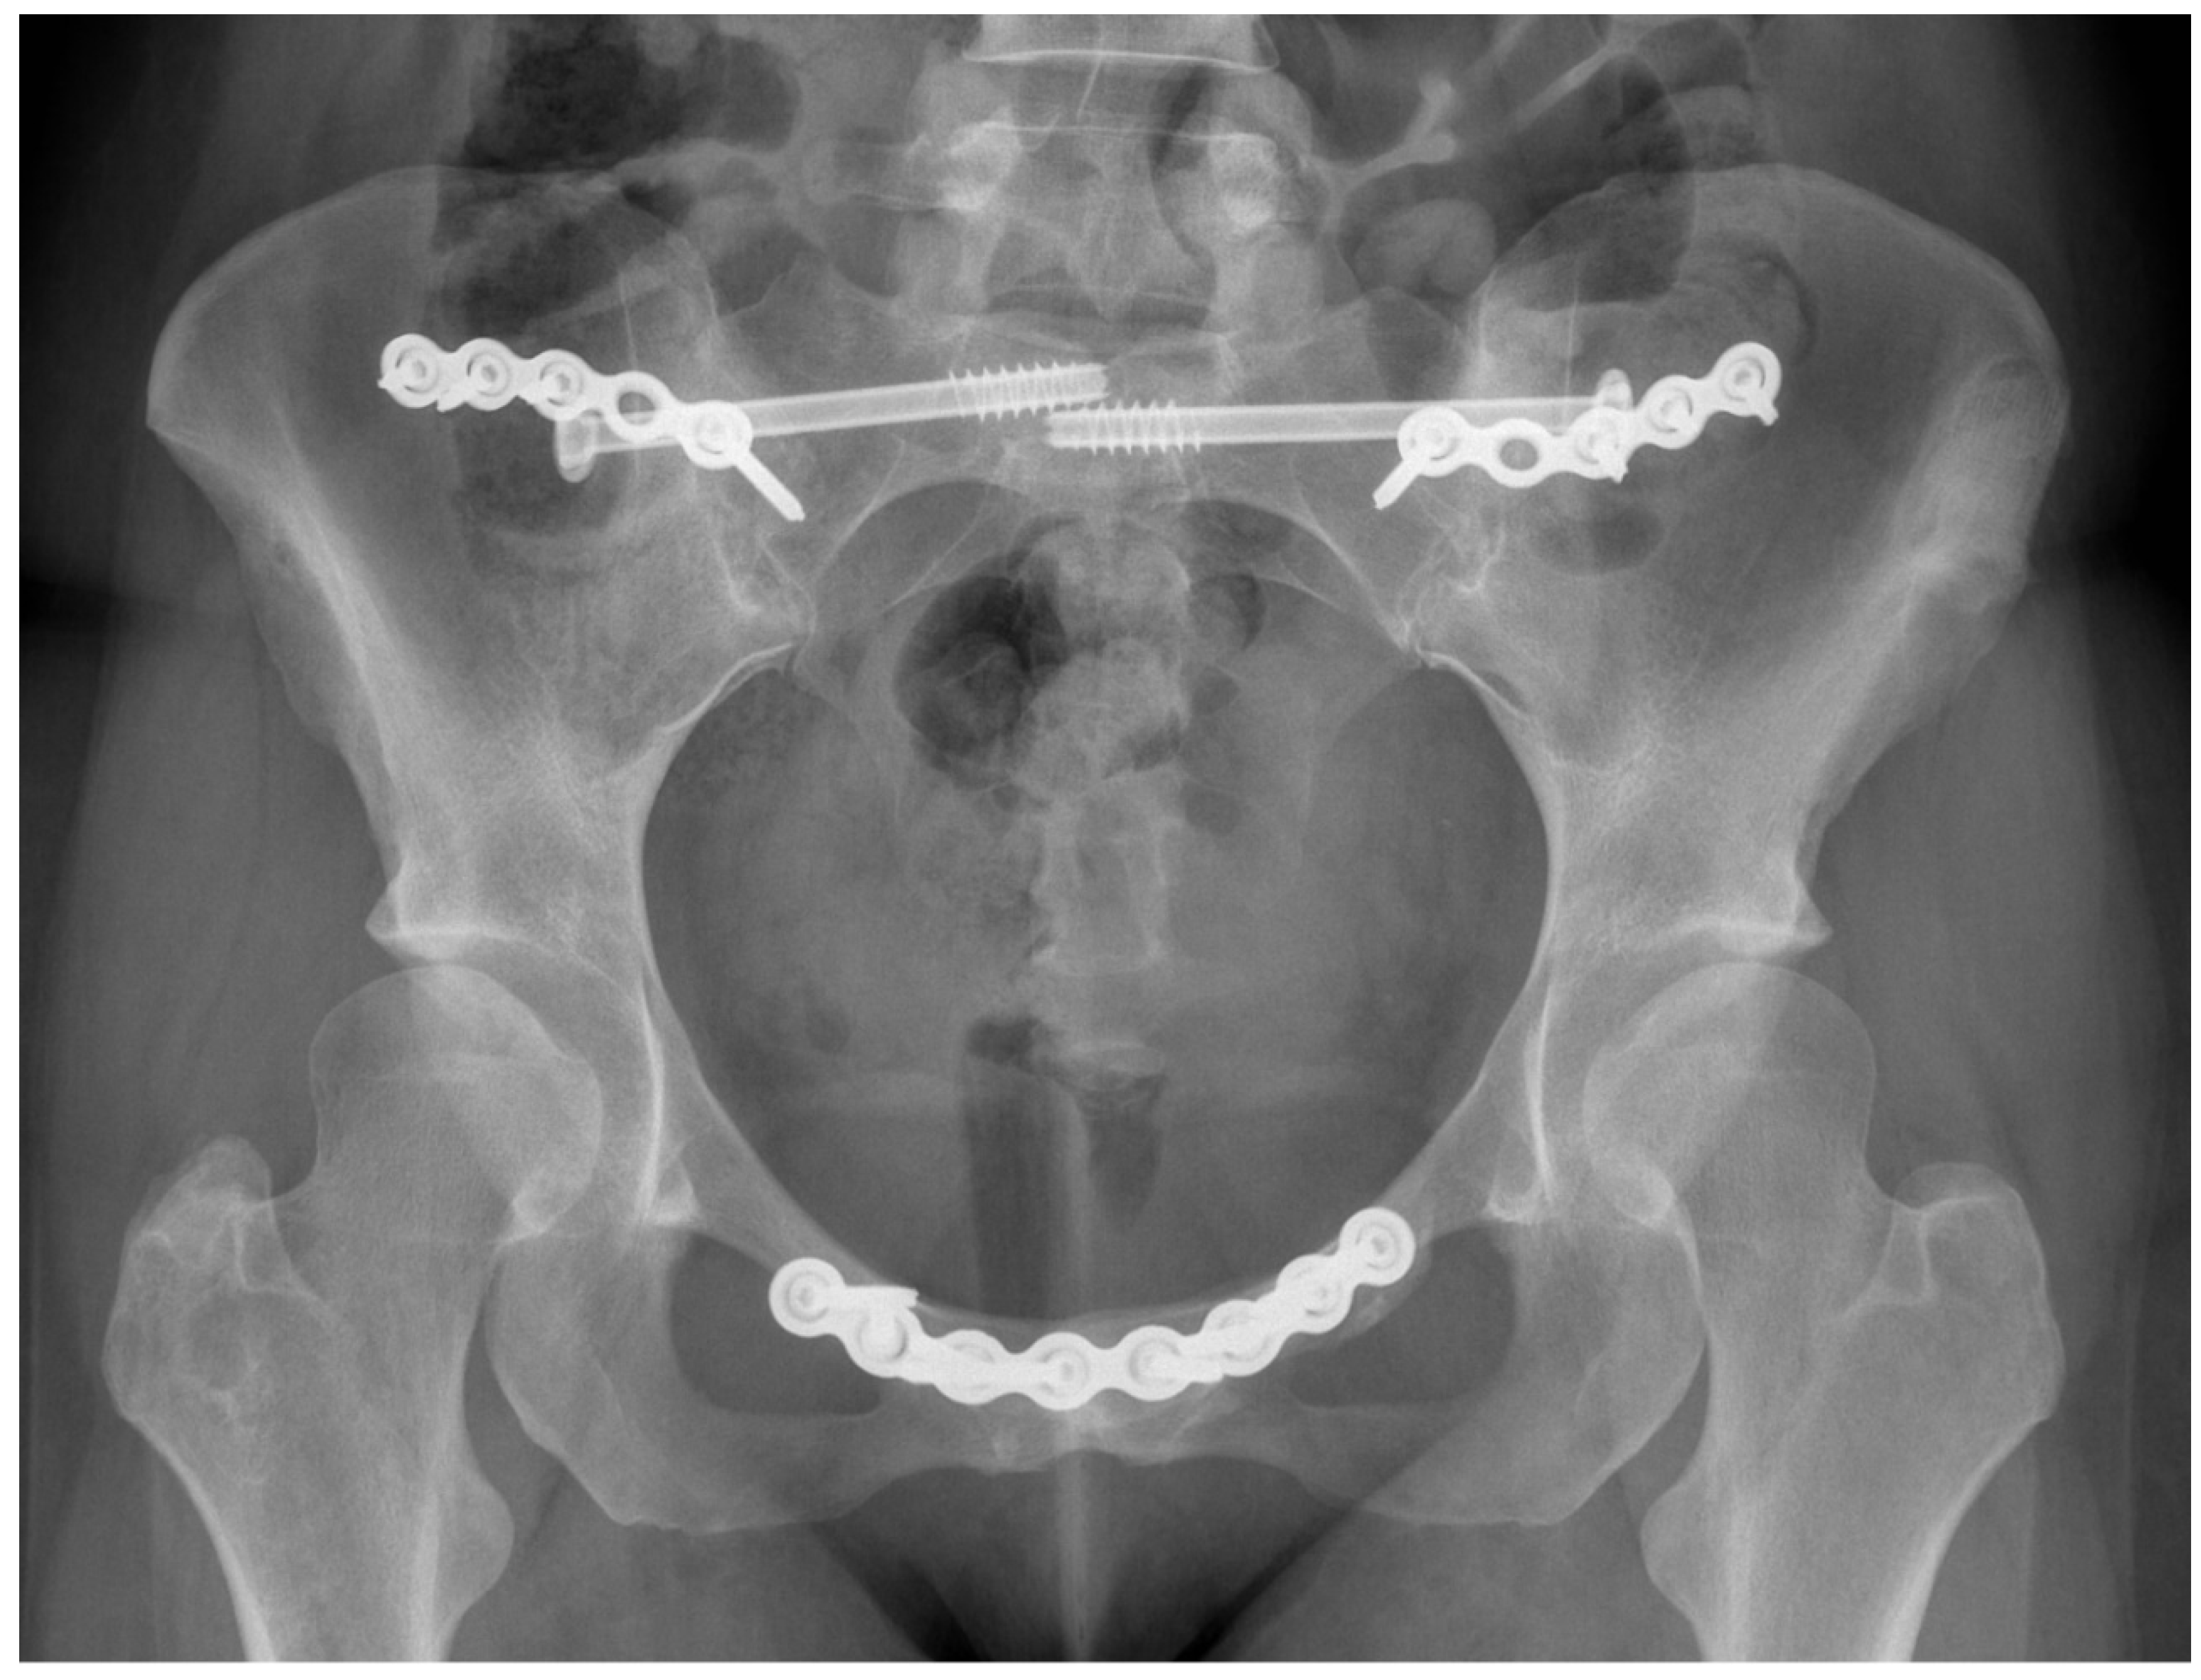

- Van Zwienen, C.M.; Van den Bosch, E.W.; Snijders, C.J.; Van Vugt, A.B. Triple pelvic ring fixation in patients with severe pregnancy-related low back and pelvic pain. Spine 2004, 29, 478–484. [Google Scholar] [CrossRef] [PubMed]